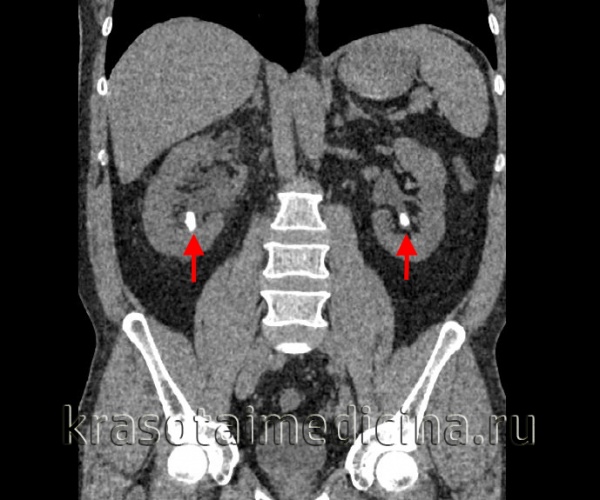

КТ ОБП и забрюшинного пространства. Плотные конкременты в нижних чашечках с обеих сторон. (фото Вишняков В.Н.)